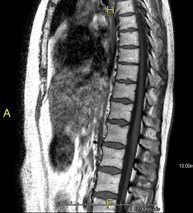

- Lumbar spine MRI

This non-invasive diagnostic procedure uses an electromagnetic field and radio waves (from a transmitter and receiver) to acquire high-definition anatomical images of the lumbar and sacral regions. It is a radiation-free procedure. Indicated for: trauma, sciatica, herniated discs, tumours, infections.